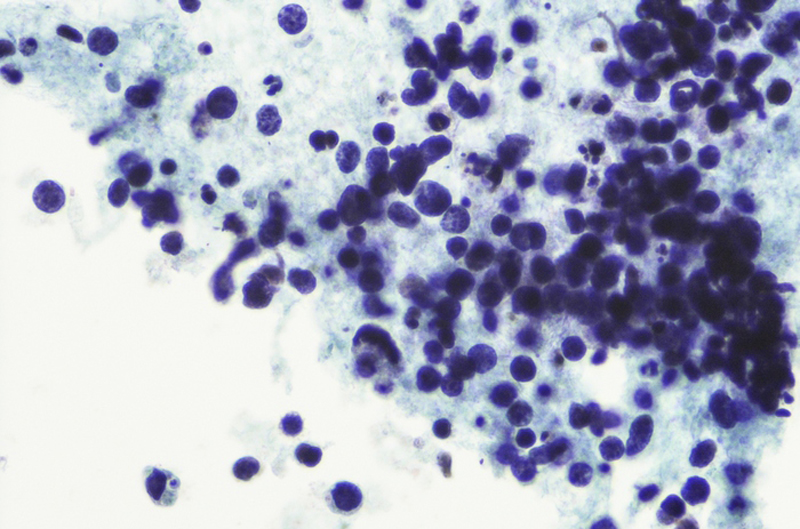

L'esposizione a lungo termine a particolati come il PM2.5 è ritenuta la causa per circa il 23% delle morti globali per cancro al polmone. Lo studio è stato condotto su 681 pazienti canadesi, fumatori e non. I ricercatori hanno quindi evidenziato una forte interazione tra inquinamento dell'aria e sesso di appartenenza nei non fumatori: essere donna aumenta infatti il rischio così come l'appartenenza all'etnia asiatica.